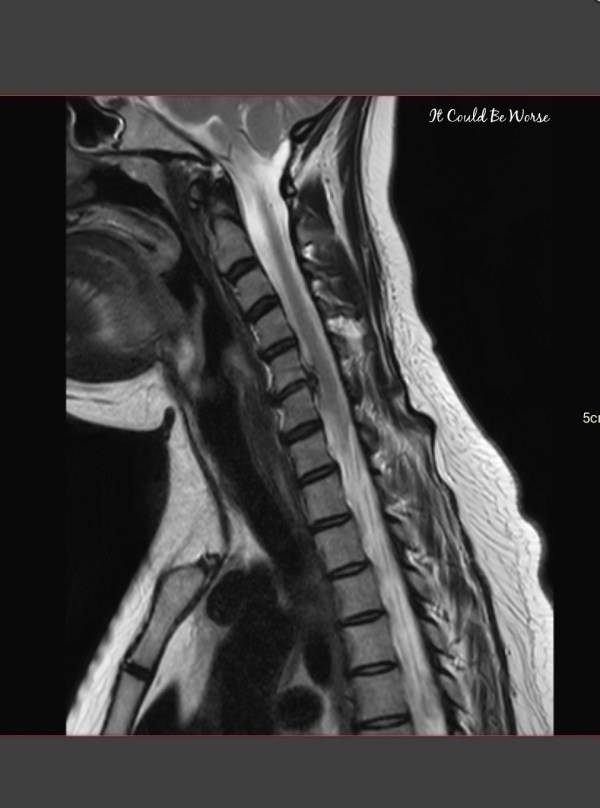

If you guys remember, I was in a car accident on February 22nd. I had been worried about that happening since I had my ACDF surgery on my spine last August - it has been my biggest fear, to be in a car accident, rear-ended, etc. Now, it has been almost 3 weeks since the... Continue Reading →